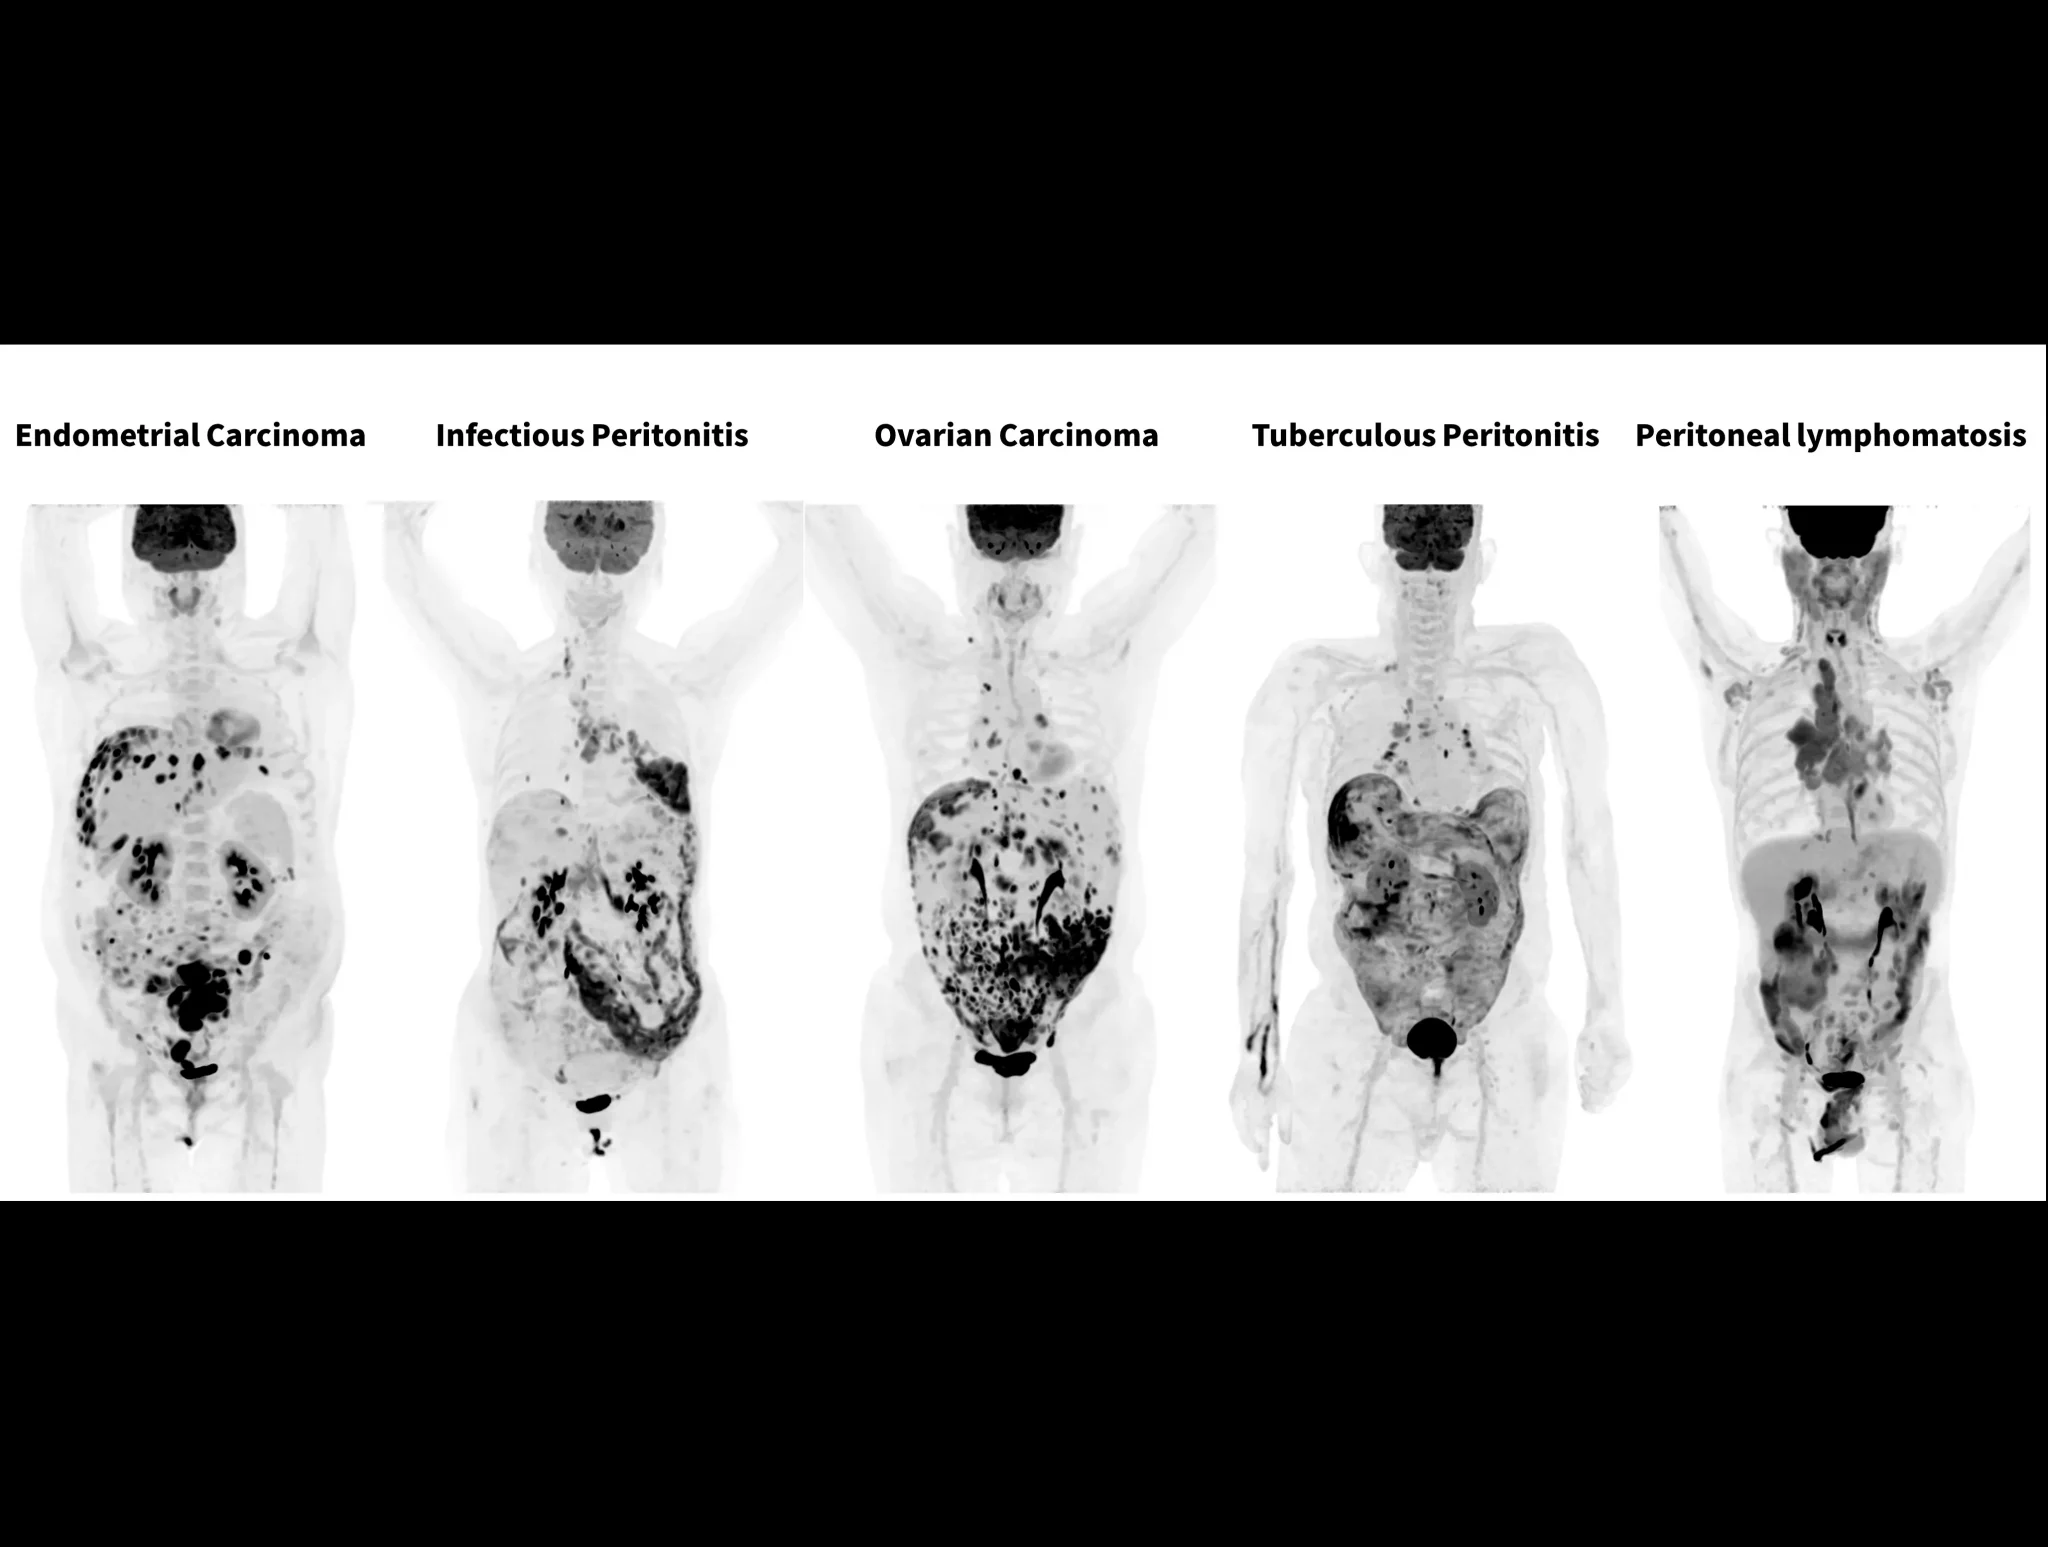

With the ultra-high system performance, uMI Panorama faces up to the challenges of tracers with different half lives and the complex scanning conditions, without compromise for image quality.

New-Tracer Imaging

Click on different tracers to see the images.

Case Gallery